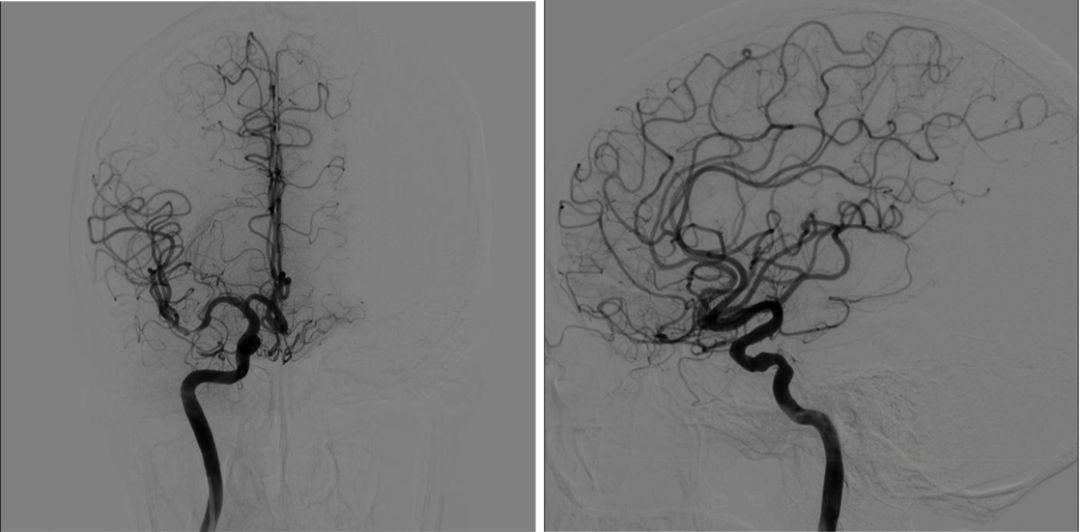

调整SIM2导管头端位置,将造影导丝放入降主动脉,SIM2管随造影导丝进入降主动脉;撤回造影导丝,顺时针或逆时针轻轻扭动SIM2导管,让其成袢;慢慢回拉成袢的SIM2导管,让其头端跳入左锁骨下动脉口,造影剂冒烟证实后,适当调整导管头端位置和张力后,行左侧锁骨下动脉造影;若有需要,可沿导管置入泥鳅导丝超选进入左侧椎动脉,行左椎动脉超选造影;旋转并内送SIM2导管让其再次成袢,缓慢回拉并适当旋转导管,让导管头端自然跳入左侧颈总动脉,必要时可适当旋转导管,帮助其寻找到左侧颈总动脉;旋转导管解袢,行左侧颈总动脉造影,或用泥鳅导丝协助超选进入左侧颈内动脉,行左侧颈内动脉超选造影;旋转并内送SIM2导管让其再次成袢,缓慢回拉并适当旋转导管,让导管头端自然跳入无名动脉;导管进入无名动脉后,边回拉边冒烟,让导管头端对准右侧颈总动脉并顺利进入,解开导管袢,必要时用泥鳅导丝助其超选进入右侧颈内动脉,完成右侧颈内动脉造影;回拉导管至右侧锁骨下动脉,冒烟证实在右侧椎动脉口附近时,行右侧锁骨下动脉造影;路途下,用泥鳅导丝把SIM2管带入右侧椎动脉,行右侧椎动脉超选造影。

右侧颈内动脉超选造影

左侧颈内动脉超选造影